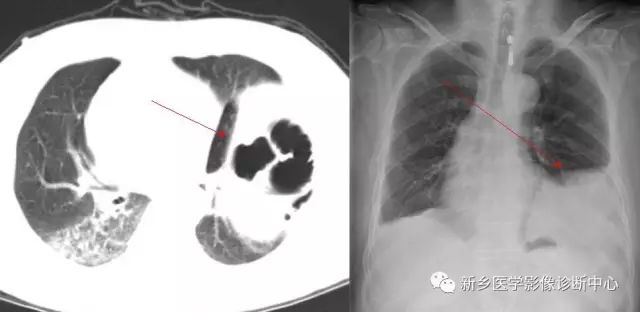

CT:贲门级部分胃体组织通过食管裂孔进入胸腔内,位于膈上,其上段食管明显扩张。

CT:食管裂孔疝以食管下端纵隔内有疝囊检出为直接征象。疝囊以假肿块样改变为特征,可有软组织密度肿块,也可表现为囊性液体密度影,部分疝囊以食管下端扩张改变为影像表现,经食管裂孔向膈下胃腔延续为主要特点。疝囊外壁光整,内壁可呈锯齿状,可见胃黏膜影像。胃壁充盈好则厚度较薄,疝囊带状管腔扩张样改变,内有潴留食物;充盈不佳者囊壁较厚,表现为软组织团块样影,内有少量液体或气体影。采用CT增强扫描,胃壁与疝囊囊壁均匀一致。

如发现疝囊壁不规则增厚,外壁不光整,周围淋巴结肿大等征象,高度怀疑食管裂孔疝合并肿瘤。需进一步胃镜活检检查。食道静脉曲张CT平扫表现为食管下端管腔轻度扩张、管壁增厚,黏膜增厚类似胃黏膜,易误诊,食道静脉曲张是肝硬化、门静脉高压的重要并发症,常与胃底静脉曲张并存;CT增强扫描显示食道下段、胃底部扩张血管影,同时有肝硬化表现,结合临床病史鉴别不难。食管下端憩室表现为囊袋状突出食管腔外的局部管腔扩张,内有气液平面,但胃腔与食管壁间无延续的胃黏膜像,且憩室下方正常食管段明显变窄,隔下有呈扩大改变的胃腔。